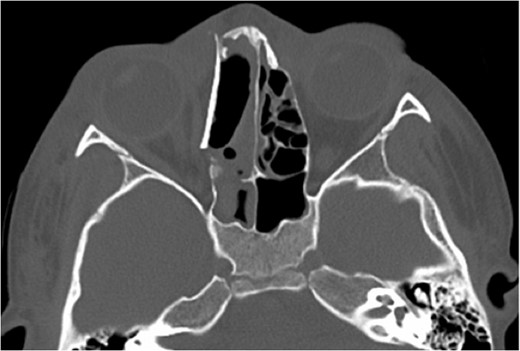

A 6-year-old boy with a background of asthma presented to a tertiary paediatric unit in May 2016 with a 3-day history of right eye pain, proptosis and erythema under the care of the ENT team. A provisional diagnosis of a periorbital cellulitis was made secondary to ethmoid sinusitis and management with intravenous antibiotics (ceftriaxone), intranasal steroids, saline douches and topical oxyxlometazoline was initiated. Ophthalmological assessment demonstrated normal colour vision, acuity and light reflexes bilaterally but also proptosis-related ophthalmoplegia. Computed tomography (CT) imaging of the orbits and paranasal sinuses demonstrated complete opacification of the right-sided paranasal sinuses and compromise of the right frontal and ostiomeatal unit. In addition there was an expansile abnormality centred on the ethmoidal labyrinth with bony remodelling of the lamina papyracea and a subperiosteal collection adjacent to the medial orbital wall (Figs 1 and 2). The most likely diagnosis was felt to be an infective process with mucopyocele formation complicated by a subperisoteal post-septal collection. An MRI scan with gadolinium of the orbits and sinuses confirmed the unilateral pattern of sinus opacification within the right frontal, ethmoids and maxillary sinus. The lesion demonstrated multiple fluid–fluid levels and peripheral enhancement (Figs 3 and 4). The patient was treated by endoscopic drainage of the lesion, which revealed only blood. He initially had some improvement of his proptosis but recurred within a few days and so further, more extensive endoscopic debridement was performed.

Axial post-contrast CT demonstrating the peripherally enhancing right-sided intra-orbital subperiosteal component. The expansile lesion centred on the right ethmoidal labyrinth demonstrates a faint fluid–fluid level.